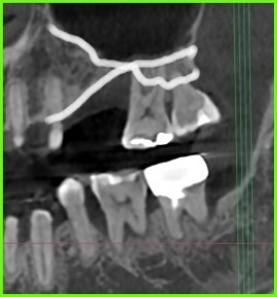

사진 1) 잇몸뼈가 수직적으로 너무 얇은 상태입니다.(하얀색 실선)

사진 2) 임플란트를 식립하려면(초록색 네모), 상악동 거상술을 통해 뼈를 만들어 줘야 합니다.(노란색 실선)